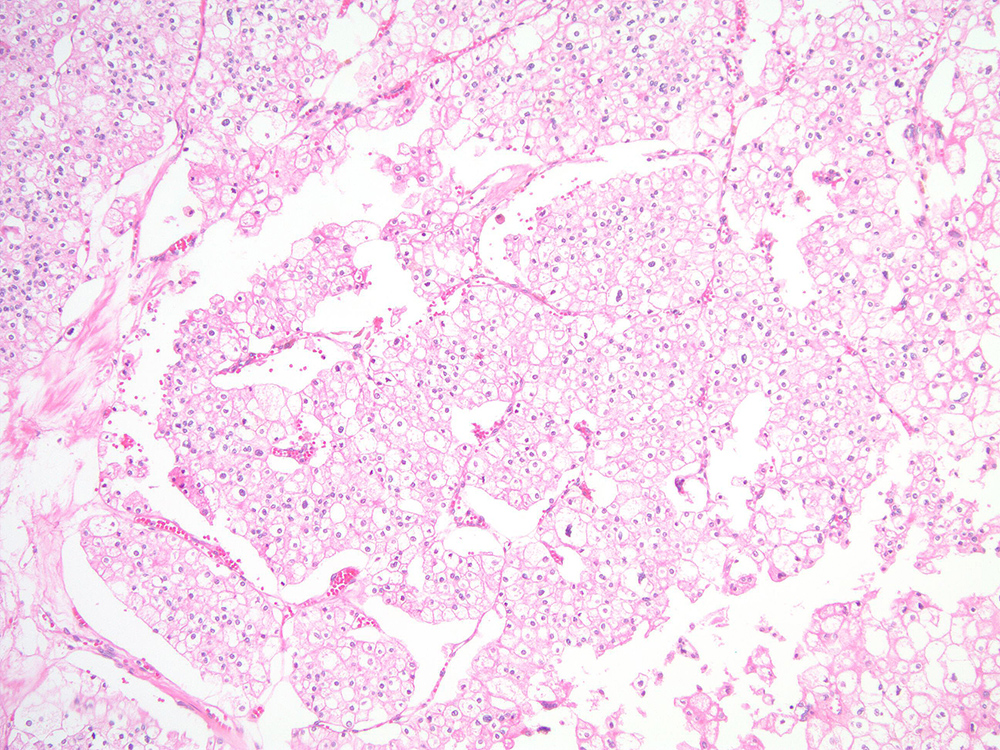

Case ID: 752

Consensus grade: I would not grade this tumor

Case description (by case creator):

renal mass